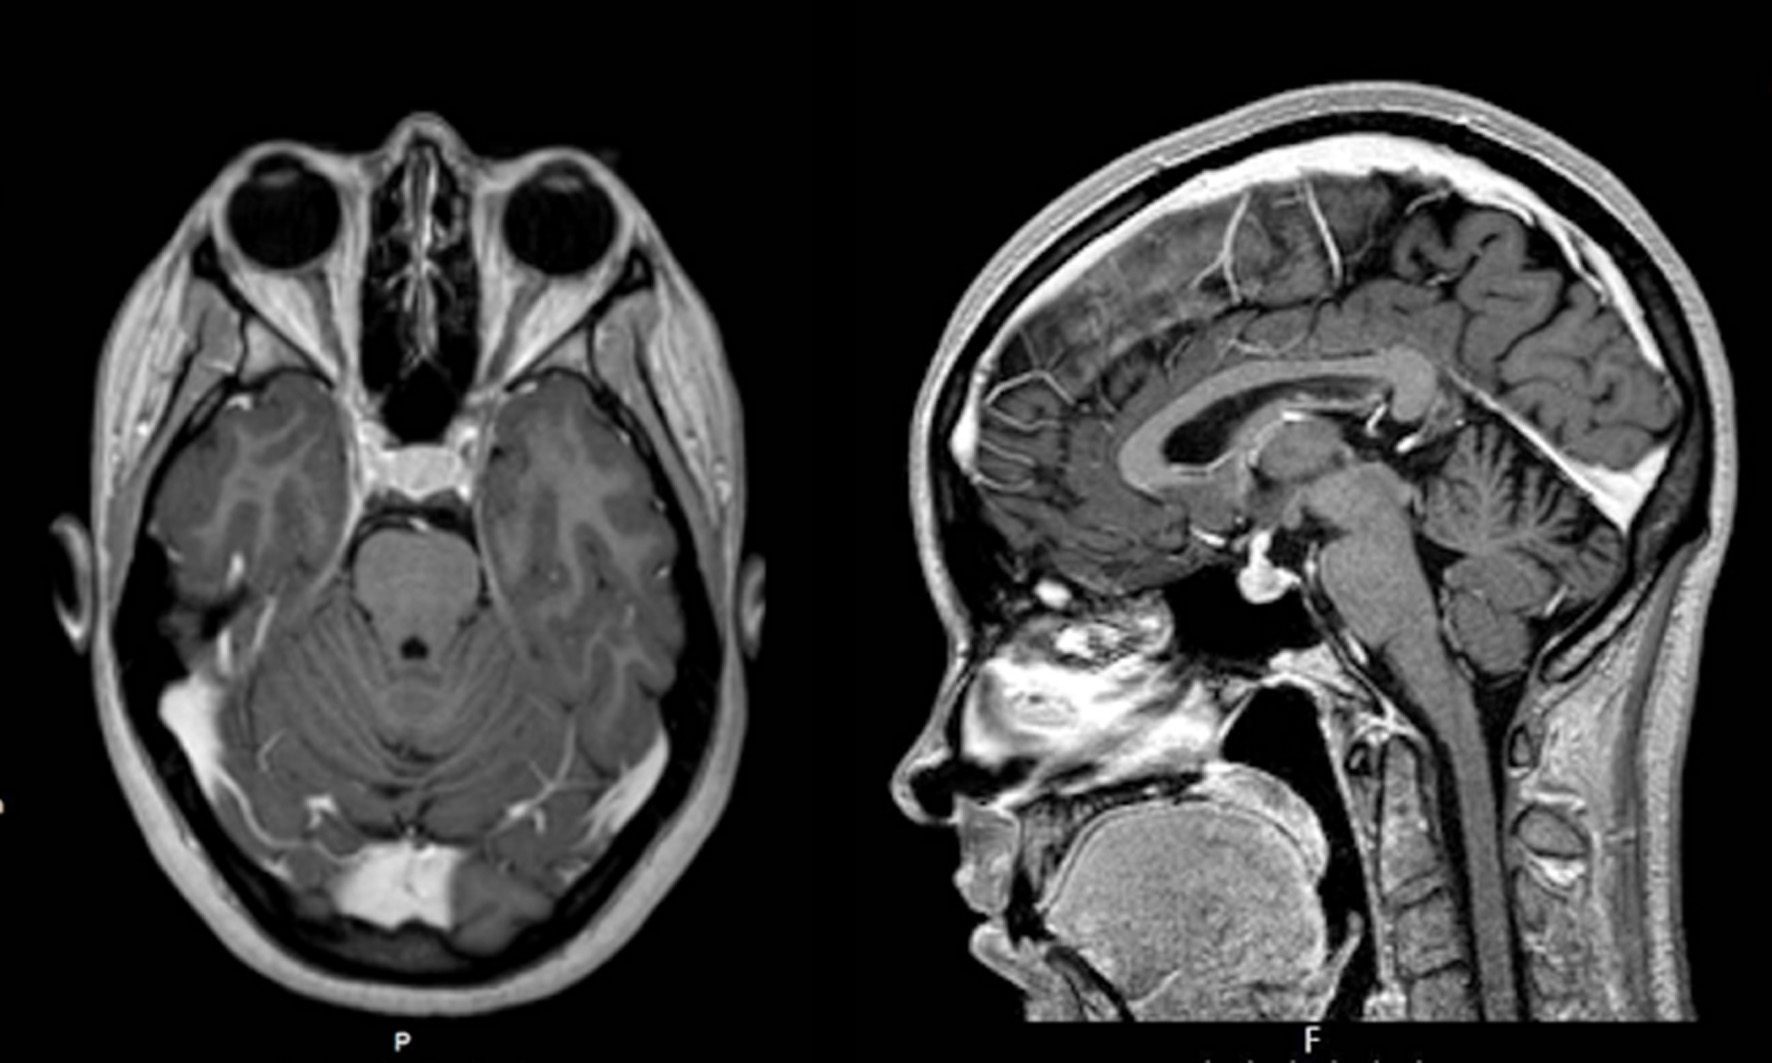

Since she was a health professional working in a public central hospital in Lisbon, with easy access to medical care, a head MRI study had already been obtained that revealed a large intra-sellar mass with 19 × 13 mm, extending up until the optic nerves with no lateral invasion of the cavernous sinuses. That mass representing the whole pituitary gland was hypointense in both T1- and T2-weighted sections with homogenous uptake of the contrast. There was a widening of the pituitary stalk and the neurohypophysis could not be defined clearly (Fig. 2).

![]() Click for large image  | Figure 2. First MRI study showing diffuse enlargement of the whole pituitary gland. MRI: magnetic resonance imaging. |

A new MRI did not reveal any pituitary abnormalities except for the persistent pituitary stalk widening (Fig. 4).

![]() Click for large image  | Figure 4. Last MRI study with marked widening of the pituitary stalk. MRI: magnetic resonance imaging. |

Imagiological findings are also discordant. In classic cases a small (5 mm) round hypodense (T1-weighted sections) lesion is found; it may be hyperdense in T2-weighted sections and may or not uptake the contrast [15, 16, 22, 47, 48]. Instead in this case a large (19 × 12 mm) lesion that seems to include all the pituitary with pituitary stalk widening, no clearly visible neurohypophysis bright spot and hypointense in both T1 and T2 is found with homogenous contrast uptake. This might suggest either corticotroph hyperplasia (although evidence for CRH oversecretion is lacking as noted), silent corticotroph macroadenomas (but there is clear analytical evidence for hypercortisolism) or mixed type corticotroph adenomas (but no evidence for other hormone secretion is found) [26-28, 30]. Most interestingly is the pituitary stalk widening; this finding has been reported in relation to granulomatous or immune-mediated pituitary diseases in regard with hypopituitary states [15, 16]. Given the global involvement of the pituitary it may instead in this case correspond to the enlargement of the pars tuberalis that surrounds the pituitary stalk.

Surgery was however ineffective, as could be appreciated early in the postoperative period [16, 24, 50-52]. At 6 months, there is clear evidence for disease persistence after surgery with marked non-suppressible hypercortisolism. Hypercortisolism was however apparently reduced to almost half, and this would favor corticotroph hyperplasia, or partial remotion of the adenoma [16]. Furthermore there is now no apparent abnormality of the pituitary except for the persistent pituitary stalk widening, so that presumably that widening at least contributes to the sustained autonomous hypercortisolism, even if a non-visible microadenoma cannot be excluded.